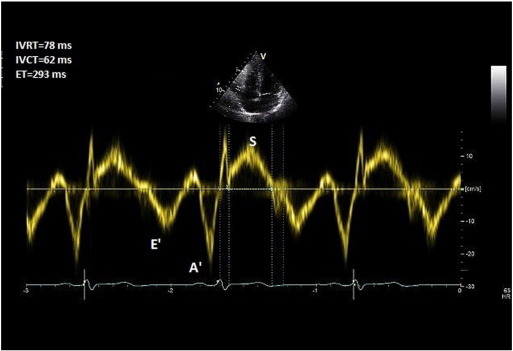

8. Tei index and TR measured PASP

8.1. Method

In the apical 4-chamber view, TDI is deployed on the RV free wall and a 3–5 mm pulse wave Doppler is obtained approximately 1 cm from the tricuspid annulus. Isovolemic contraction time (IVCT), isovolemic relaxation time (IVRT), and ejection time (ET) of the RV are then measured (Fig. 8 ). Alternatively, these measures could be obtained from CW Doppler across the RV inflow/TR jet. Tei index is measured by the formula: Tei Index (RV) = IVRT + IVCT/ET.

Fig. 8

Fig. 8.

Measurement of Tei index.

8.2. Common pitfalls

The method was studied in small groups of patients and has not yet been validated in larger sample sizes [28]  and [29] . Tei index is, however, proven to prognosticate patients with pulmonary hypertension [30] .